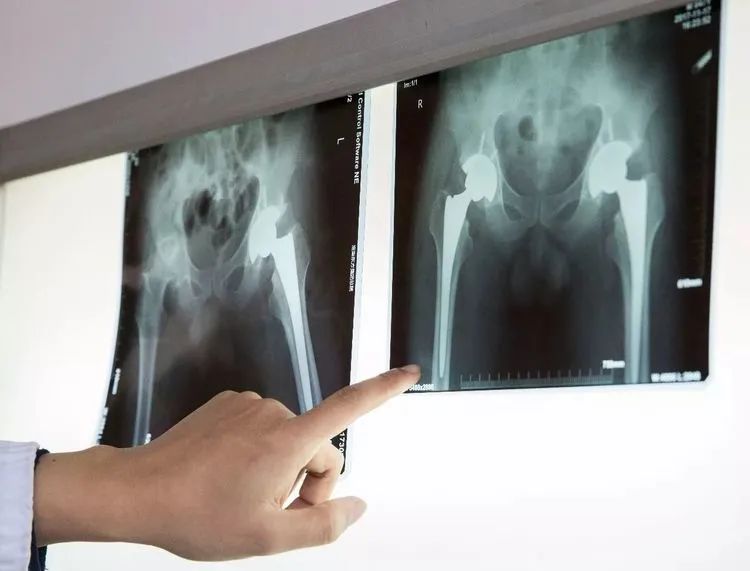

家住壽縣的馬大娘,十五年前開始出現(xiàn)雙側(cè)髖關(guān)節(jié)疼痛,隨著時(shí)間的推移,疼痛越來越厲害,腿不能屈,蹲也蹲不下。經(jīng)人推薦,馬大娘一家來到了淮南東方醫(yī)院集團(tuán)廣濟(jì)醫(yī)院骨科就診。完善檢查后,明確診斷為“雙側(cè)先天性髖關(guān)節(jié)發(fā)育不良(DDH)、雙側(cè)股骨頭無菌性壞死”,骨科王懷波主任邀請(qǐng)廣濟(jì)骨科首席專家方成教授共同開展術(shù)前討論,迅速為其擬定“右側(cè)全髖關(guān)節(jié)置換術(shù)”。

隨后,在手術(shù)室團(tuán)隊(duì)的配合下,為其行腰硬聯(lián)合麻醉下“右側(cè)全髖關(guān)節(jié)置換術(shù)”,方成教授主刀,王懷波主任協(xié)同,熟練地切開、顯露,切除、清理、安裝......手術(shù)十分順利。

術(shù)后馬大娘恢復(fù)良好,正在積極的進(jìn)行術(shù)后康復(fù)訓(xùn)練。家屬告訴筆者,“年初來過一次,當(dāng)時(shí)醫(yī)生說腦梗(腦梗塞急性期),不能手術(shù)?,F(xiàn)在腦梗好了(腦梗塞恢復(fù)期),所以來手術(shù)了。早就聽說東方集團(tuán)好,醫(yī)生技術(shù)好,態(tài)度也好。廣濟(jì)醫(yī)院離我們近,來這里看病方便......”